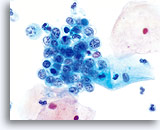

在传统的巴氏涂片上,细小的异常细胞通常会与 HSIL 相伴出现;这些细胞通常会被包裹在粘液中,或“隐藏”在背景物质内的细胞团内。由于在采用 ThinPrep 系统时,粘液和细胞碎片会经过分散处理,因此由该系统处理的标本会看起来有所不同。在使用倍镜读片时,细小的 HSIL 细胞会以单个细胞或以小细胞团的形式,在细胞的沉积背景中“凸显”出来。这些细胞应能提醒您:应更加密切地关注所呈现出的细胞物质,并查找是否有更多可供诊断的高度上皮细胞团。只要在低倍镜下看到这些细小的单个细胞或细胞团,就可在高倍镜下对这一部分玻片进行“筛查”。ThinPrep 系统的分散处理流程不会使真正的上皮细胞团发生破碎(因为高度病变存在异型性),并将会呈现出更多的单个细胞,注意到这点是至关重要的;这些是寻找病变细胞的“线索”。

对于 ThinPrep® 涂片检测,HSIL 的诊断标准如下: 单个细胞(HSIL 最重要的标准)是不对称三维胞核结构异型的表现。为掌握 HSIL 诊断,必须对此概念有明确的理解。不良胞核的结构将发生异型变化;对于这些胞核而言,只有对单个细胞的焦距进行上下控制,才可对这些胞核做出彻底的诊断。此概念是最难以在书本图片(二维页面)上展示的;然而,这却是最为重要的。

试想想对一个微缩的花椰菜、握紧的拳头、棒球或扁桃腺的焦距进行上下对焦。葡萄干的表面看起来像什么?正常胞核的形状相对较圆或呈椭圆形,并且其表面也是平滑的。不良细胞将具有凸起、凹陷、褶皱、裂纹和奇怪的隆起。这些非常明显的异型性是异生性(特别是 HSIL)的基本特征;而由于传统的细胞涂片在固定和染色过程中会存在各种干扰物质,上述的细节往往会在传统的细胞涂片丢失 , 这样令传统涂片的诊断能力造成限制。

这些三维细胞结构的异型性可与简单的“不规则细胞核轮廓”区别开来;在 ThinPrep® 玻片上,这些将是良性细胞的一种特征表现。由于是二维的, 由于是二维的,当检查员在显微镜下上下对焦时,这些“褶皱”像裂缝或山脉般难以在胞核中心被追踪,这样会为无经验者做成相类似的假像。

在玻片上,并不是每个不良细胞都会呈现出这些三维结构的异型性;但是,在这些玻片上,这些异型性至少会在一些细胞中较为明显。显然,染色质量直接关系到是否能够看到胞核“内部”。(与传统的巴氏涂片相比,所有的 ThinPrep® 涂片检测都使得细胞变化更为明显;但如果对反应物进行过度染色,或有轻微腐败,都将对这种最为重要的评估标准造成直接影响)。此外,与细胞凹陷或简单的褶皱(会达到胞核的全部宽度,具有“相似本体”,并会造成一定的难度)相比,这些三维结构的缺陷应该是不对称的。由于这些胞核的三维异型性能够得到放大,因此能够为 HSIL 诊断提供依据。